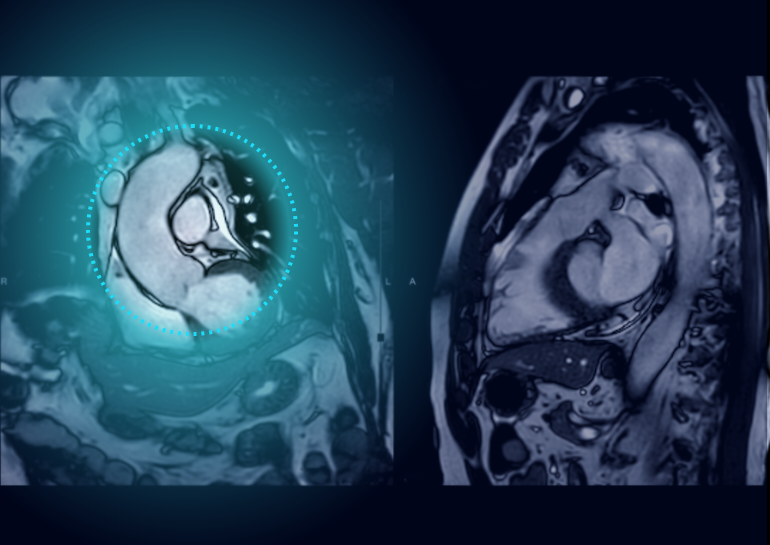

Automated Cardiac Image Analysis and Interpretation

Dyad Medical Inc. |